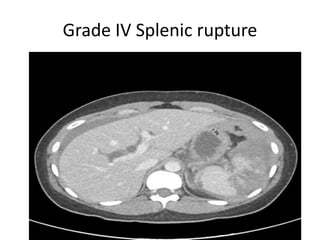

CT grading of splenic rupture.

• In it splenic lacerations appears as linear low

attenuation defects that contrast well with

high attenuation vascular spleen.

• Intra splenic hematomas appear as more

diffuse hypo-attenuating region with irregular

margins with splenic swelling.

Grade IV Splenic rupture